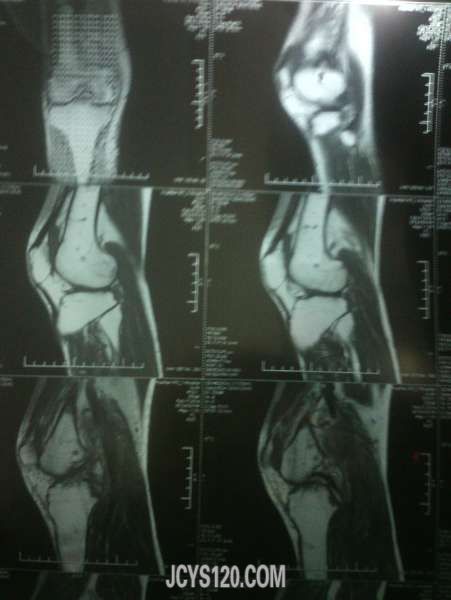

患者33岁男 因路滑扭伤!随即到医院检查,一般情况尚可,右侧膝关节。小腿腹部肿胀疼痛,磁共振影像如下,手机拍摄不是那么清楚!愿个为同行给点建议!需要做关节腔镜手术吗?有没有什么处理的方法给说说!!!

这种核磁影像不是熟悉,希望影像版版主给看看,或者楼主干脆把报告单一并发上来!

谷维素 发表于 2014-2-12 18:44 static/image/common/back.gif 这种核磁影像不是熟悉,希望影像版版主给看看,或者楼主干脆把报告单一并发上来! 谢谢回复!我也是看不太明白!毕竟见的太少~忘高手赐教!!!!

膝关节外力引起的损伤,较轻是以皮肤肌肉肌腱的损伤,严重时则出现半月板撕裂伤,髌骨的骨折。对于皮肤肌肉肌腱的损伤给予常规治疗即可,当出现半月板撕裂伤时可采取半月板的修补或切除术,这些度需要在关节镜下完成,髌骨骨折一般采用功能位的石膏固定。

体检下前后交叉韧带,侧副韧带有没有损伤,膝关节正侧位X片就够了,小腿后腹部肿明显一般是腓肠肌损伤,检查下跟腱有没有损伤,如果有问题再分别撕裂伤还是断裂伤,按情况相应处理,单肿胀用消炎止痛软胶外敷3-5天就可以了。大医院很多检查浪费。。。

片子看不懂,如果没有其他,肿胀是外伤导致静脉回流不畅所致,静滴几天丹参和七叶皂苷钠好的快些。

片子看不懂,患者没有住院。我们可以小心的给与云南白药,龙血竭胶囊治疗,但要注意观察。